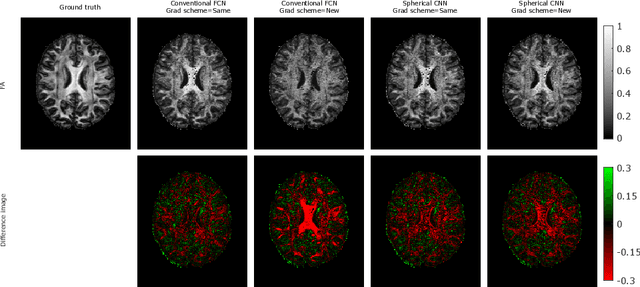

This paper demonstrates spherical convolutional neural networks (S-CNN) offer distinct advantages over conventional fully-connected networks (FCN) at estimating scalar parameters of tissue microstructure from diffusion MRI (dMRI). Such microstructure parameters are valuable for identifying pathology and quantifying its extent. However, current clinical practice commonly acquires dMRI data consisting of only 6 diffusion weighted images (DWIs), limiting the accuracy and precision of estimated microstructure indices. Machine learning (ML) has been proposed to address this challenge. However, existing ML-based methods are not robust to differing dMRI gradient sampling schemes, nor are they rotation equivariant. Lack of robustness to sampling schemes requires a new network to be trained for each scheme, complicating the analysis of data from multiple sources. A possible consequence of the lack of rotational equivariance is that the training dataset must contain a diverse range of microstucture orientations. Here, we show spherical CNNs represent a compelling alternative that is robust to new sampling schemes as well as offering rotational equivariance. We show the latter can be leveraged to decrease the number of training datapoints required.